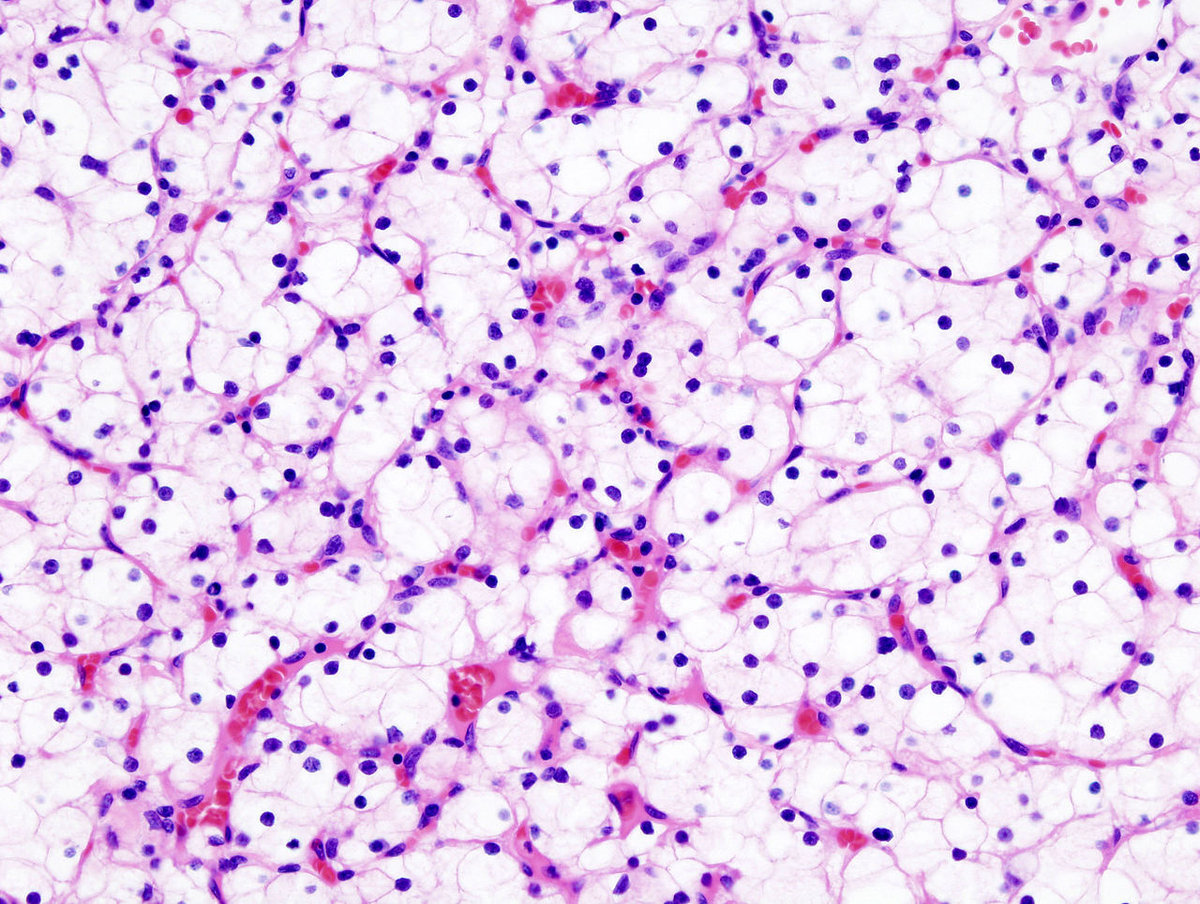

Nierenzellkarzinom

Das Nierenzellkarzinom (früher: Hypernephrom) macht etwa 85% der malignen Nierentumore aus. Weitere Formen renaler Malignome sind das vom Nierenbecken ausgehende Urothelkarzinom (10%), Non-Hodgkin Lymphome, Sarkome sowie im Kindesalter die Nephroblastome (Wilms-Tumor).